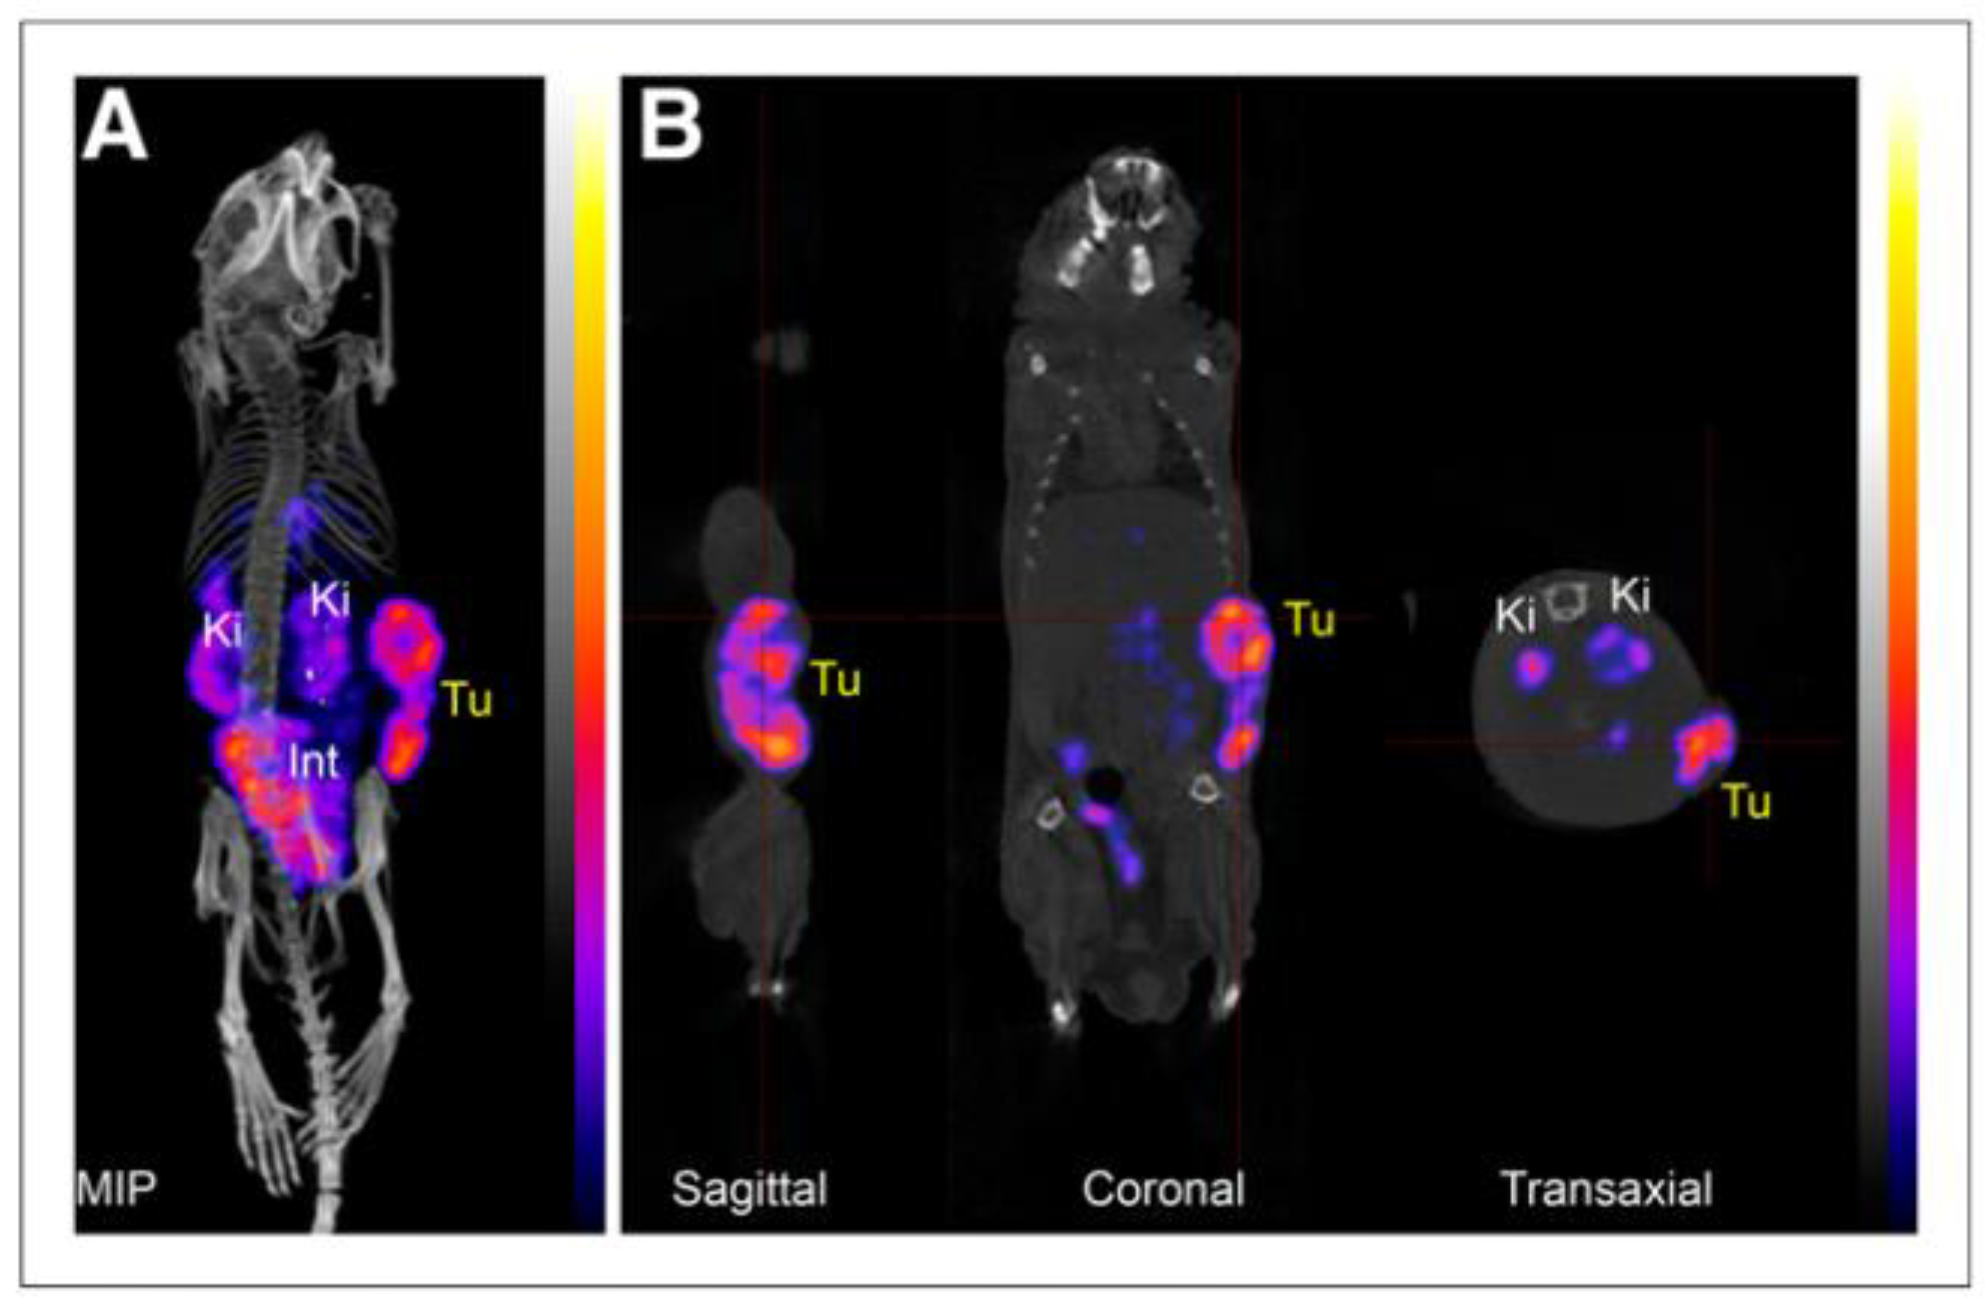

- Minn, I.; Koo, S.M.; Lee, H.S.; Brummet, M.; Rowe, S.P.; Gorin, M.A.; Sysa-Shah, P.; Lewis, W.D.; Ahn, H.H.; Wang, Y.; et al. [64Cu]XYIMSR-06: A dual-motif CAIX ligand for PET imaging of clear cell renal cell carcinoma. Oncotarget 2016, 7, 56471–56479. [Google Scholar] [CrossRef] [PubMed] [Green Version]

- Yang, X.; Zhu, H.; Yang, X.; Li, N.; Huang, H.; Liu, T.; Guo, X.; Xu, X.; Xia, L.; Deng, C.; et al. Targeting CAIX with [(64)Cu]XYIMSR-06 Small Molecular Radiotracer Enables Noninvasive PET Imaging of Malignant Glioma in U87 MG Tumor Cell Xenograft Mice. Mol. Pharm. 2019, 16, 1532–1540. [Google Scholar] [CrossRef] [PubMed]